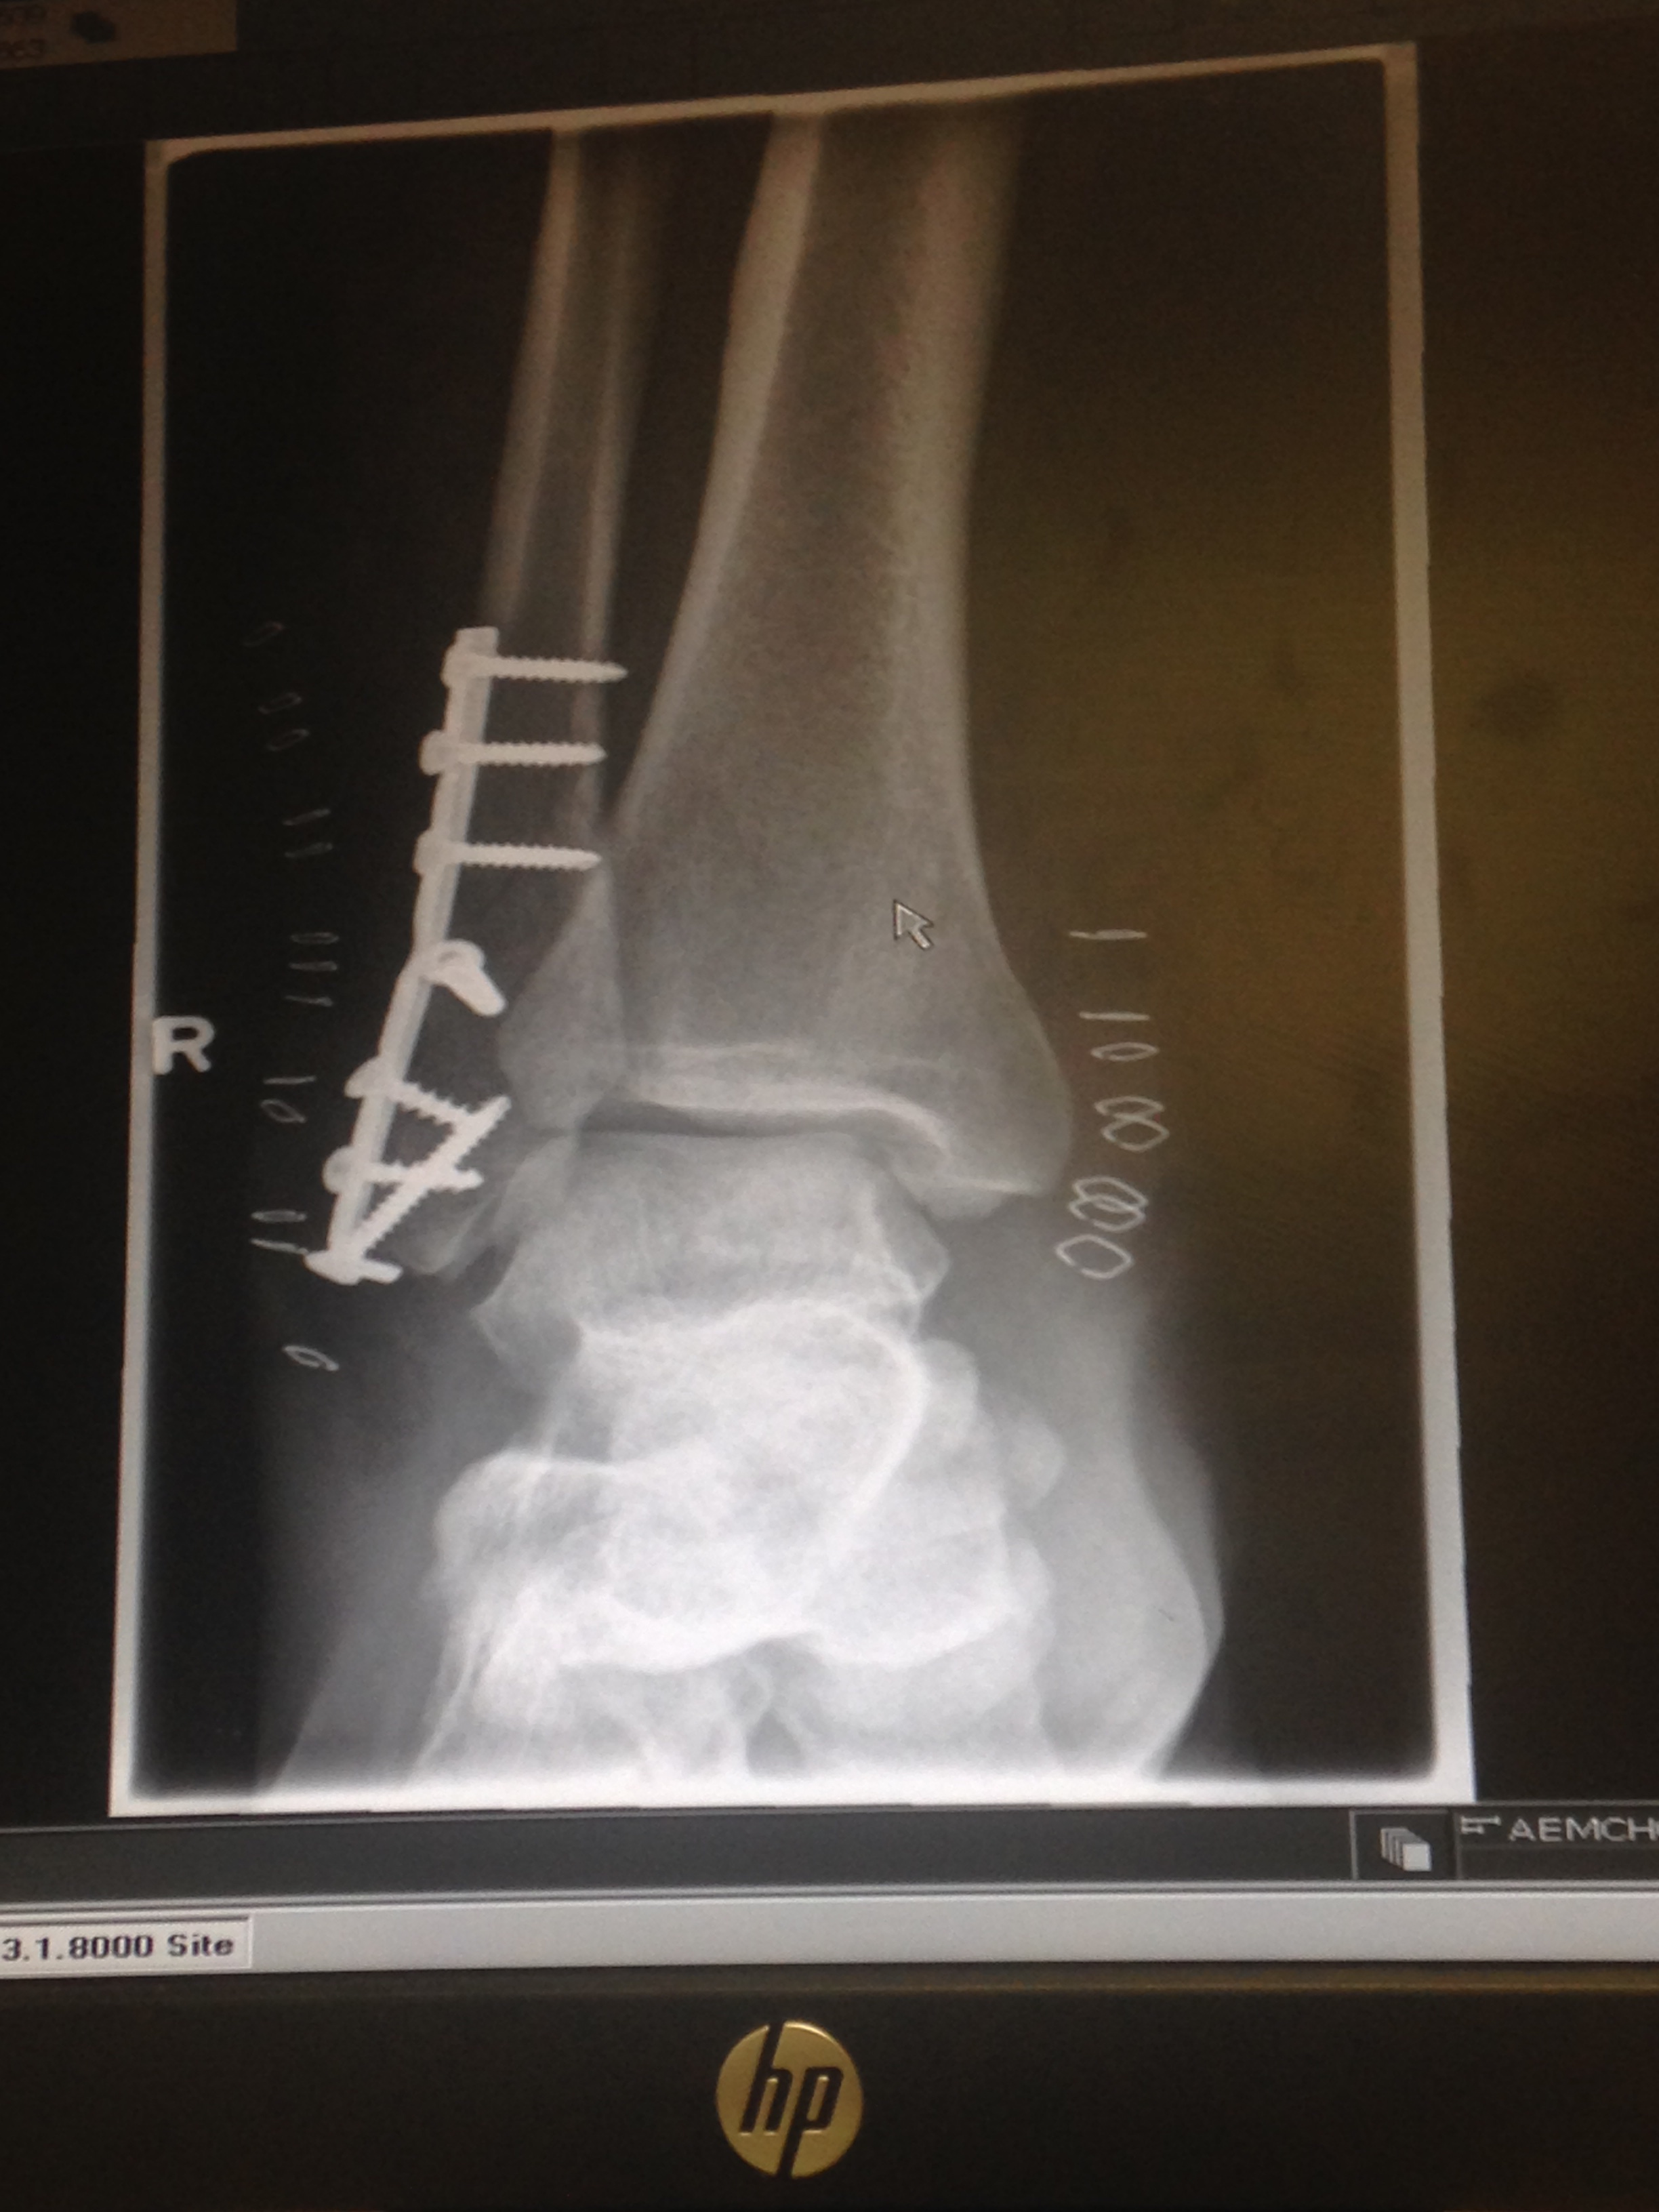

img_6316 June 18, 2019June 18, 2019 ~ twowhitelites Published by twowhitelites View all posts by twowhitelites